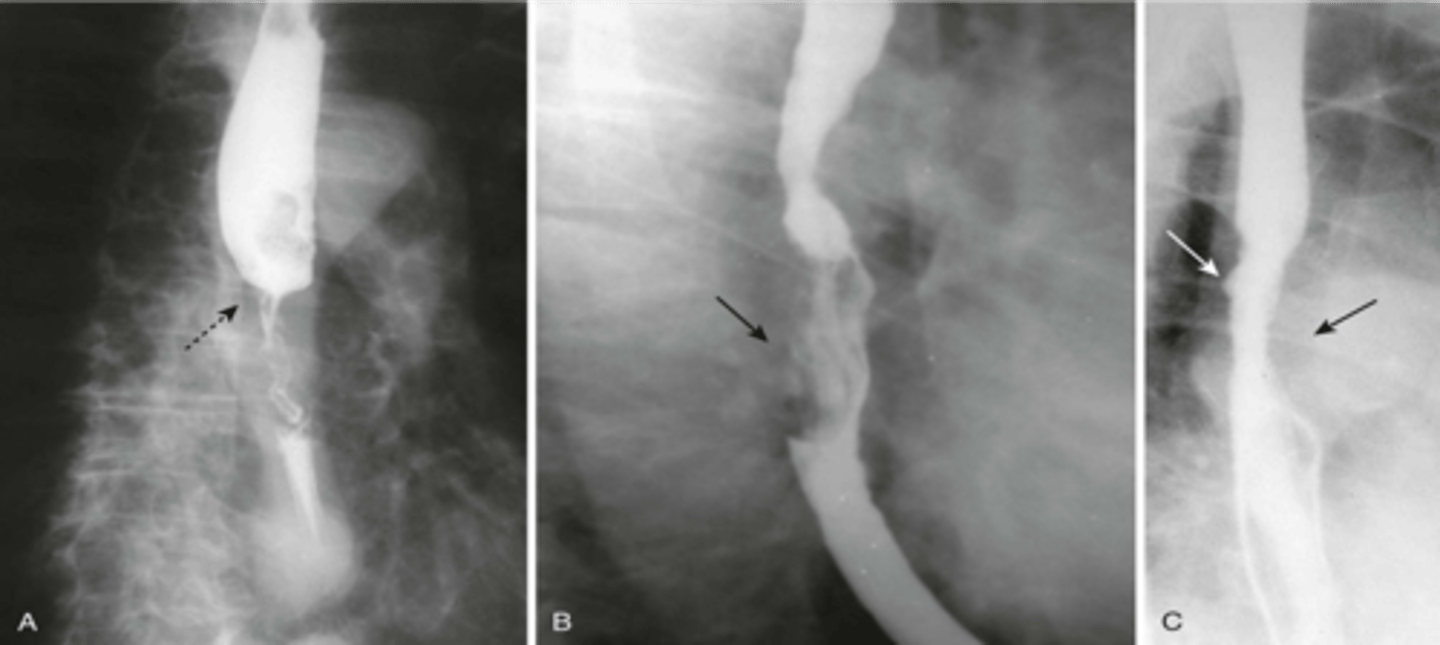

A: zenkers diverticulum

B: traction diverticulum

C: epiphrenic diverticulum